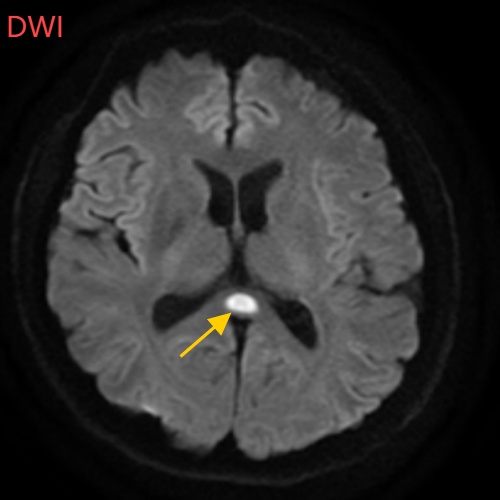

经过头部磁共振平扫、弥散、增强影像等检查

小董的影像结果显示,胼胝体压部发生病变

如果把大脑比作一座城市,胼胝体就是连接左右脑的“跨海大桥”,而胼胝体压部正是桥上的“核心枢纽”。当它因酒精、熬夜或感染“肿了”,大脑信号就会“堵车”,引发一系列“故障”。

“压部”病变:胼胝体压部是大脑里的“视觉总监”,眼睛所看到的信息传送到大脑后,由它负责反应整合成图像在脑海中呈现。“压部”发生病变后,就像电视机信号接收不良,屏幕出现雪花一样,眼睛视物就会受到影响。

除了“压部”,胼胝体的其他部位也有病变,所以小董才会出现幻听、手抖等症状。

经过一周治疗,小董的胼胝体压部病变明显好转